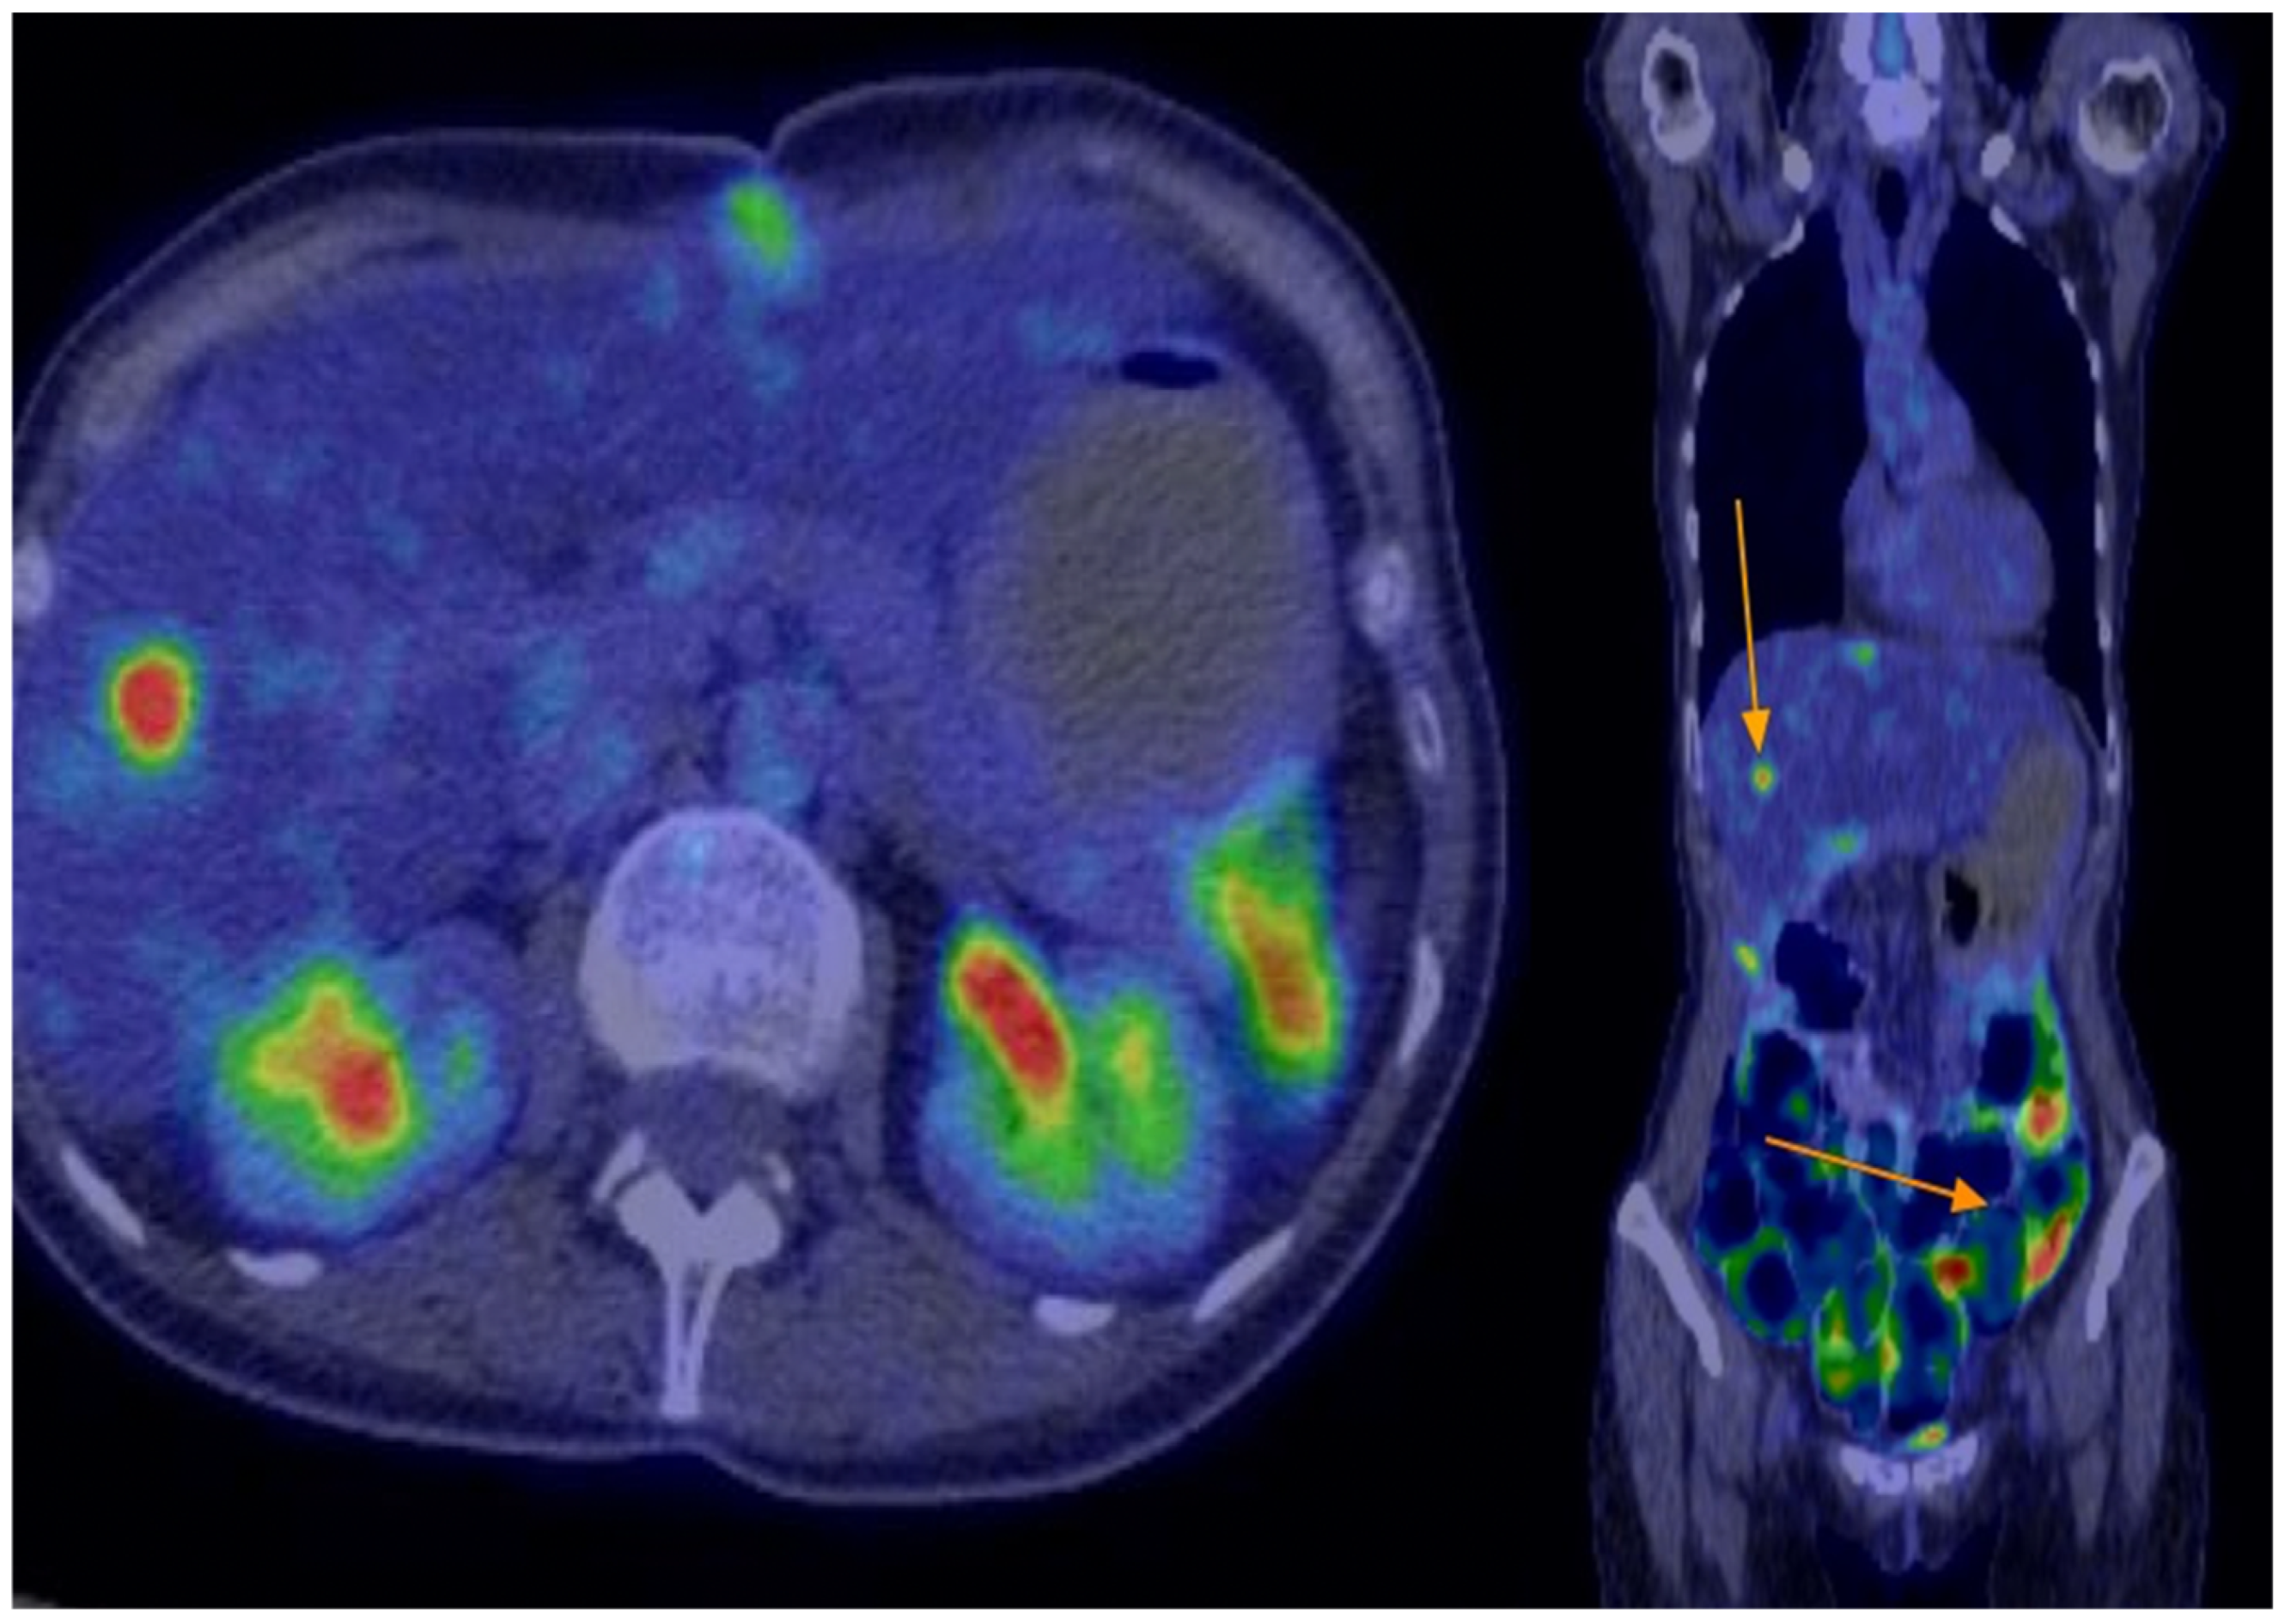

In February 2023, abdominal and pelvic MRI re-evaluation showed no signs of local tumour recurrence at the site of the entero–entero anastomosis. However, it revealed a 2 cm nodular hepatic lesion located at the junction of segments IVa and VIII, along with two additional smaller nodular liver lesions—one at the junction of segments VI and VII, and another within segment VIII. The imaging appearance of these lesions was inconclusive, and further evaluation was recommended, including PET-CT to assess metabolic activity and exclude tumour recurrence, liver MRI for detailed characterization, and a surgical consultation. At follow-up in our clinic, the patient maintained an excellent performance status, with normal laboratory results. Based on these findings, we recommended a liver MRI, PET-CT, and referral for surgical or interventional radiology consultation to consider biopsy and confirm possible disease progression. Subsequent PET-CT confirmed disease relapse, revealing metabolically active perihepatic peritoneal lesions—measuring up to 10 mm near segment IVa/VIII, with additional smaller lesions around segments VIII and VI–VII (with an SUVmax raging between 11–13).

Figure 2. Postoperative PET-CT-no residual disease.